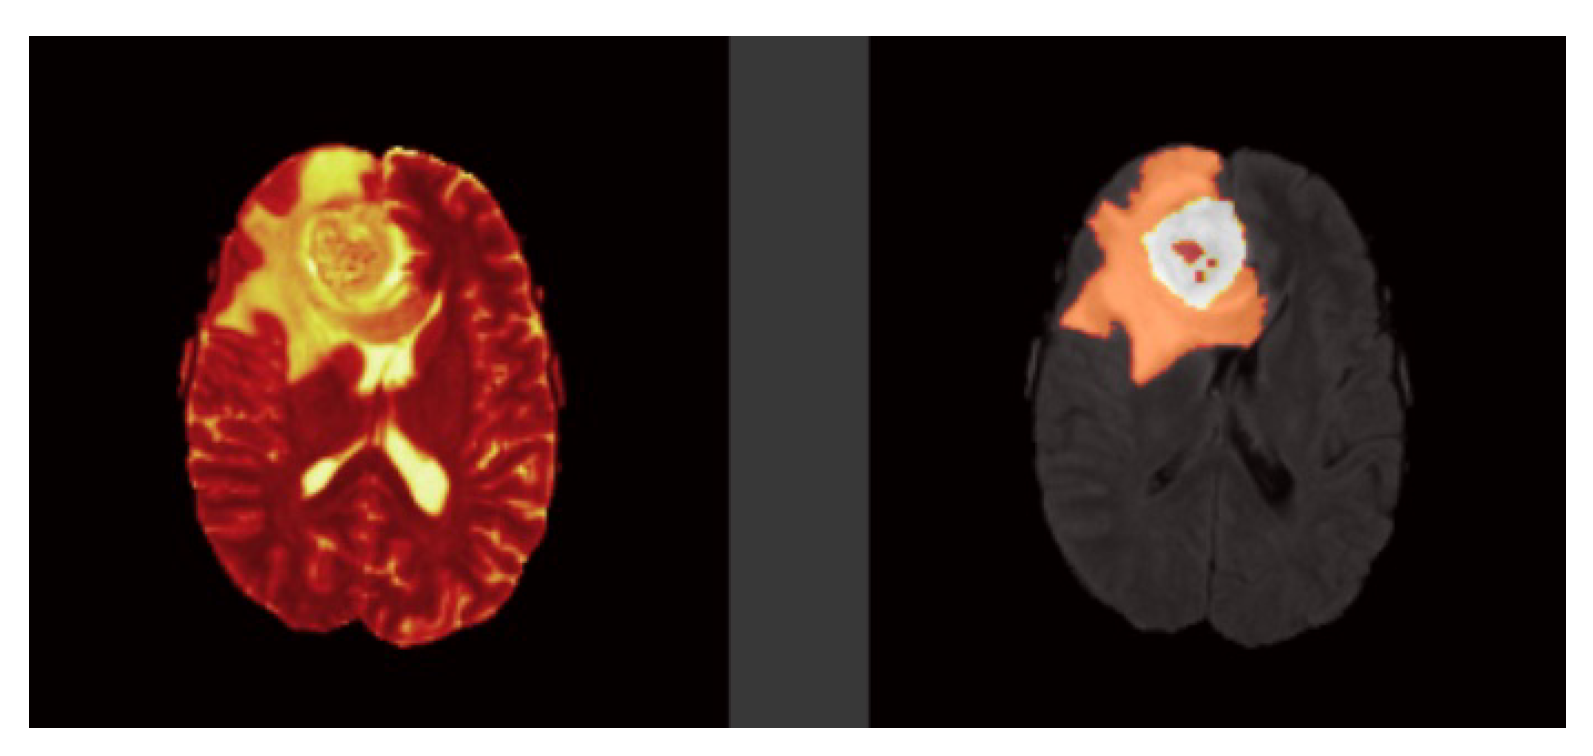

Each model is tested on the test images and the results are compared and are shown in

Table 2. The difference in performance with each model is calculated and shown in the following tables. In

Table 3 the baseline architecture is compared with the four proposed architectures. There has been a considerable performance improvement (the visual results are shown in

Figure 28,

Figure 29,

Figure 30,

Figure 31,

Figure 32 and

Figure 33). From